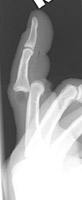

- Click on the image for a larger versionBConed AP radiograph of the second digit. Again, the PIP joint is overriding.